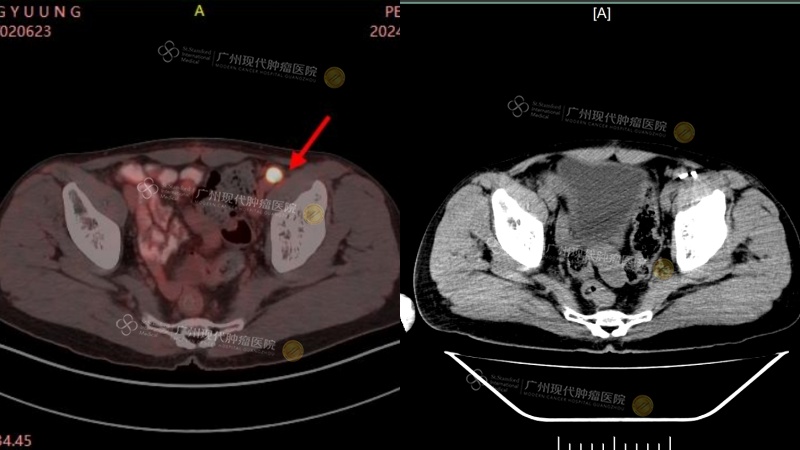

(July 2024: Lymph node metastatic lesions & placement of particles in the lymph node metastatic lesions)